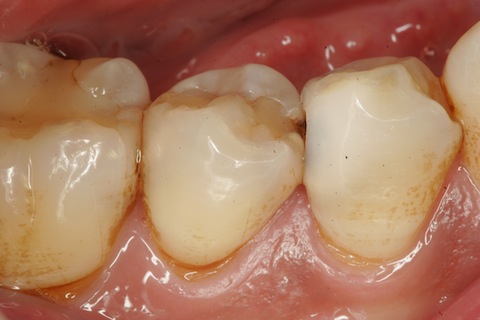

このところ労働強化をしているので、忙しくて記事をアップする時間がなかなか取れません。たくさんあるのですが、今日は1症例だけ。30代男性、右下4、遠心隣接面カリエス、自覚症状なし、歯冠内部の象牙質は溶けてしまってなにもありません。エナメル質だけが残っています。この現象は単なる酸で歯が溶けるのが虫歯ということだけでは説明できません。「虫歯の電気化学説」によれば、イオン化傾向が象牙質>エナメル質 だから、です。「虫歯の電気化学説」の要点はこちら。http://plaza.rakuten.co.jp/mabo400dc/diary/201107100002/術前歯冠内部の象牙質は溶けてしまっている。バーは向こう側の隣接面まで届く。α-TCPセメントで覆髄して、CR充填、所要時間25分。